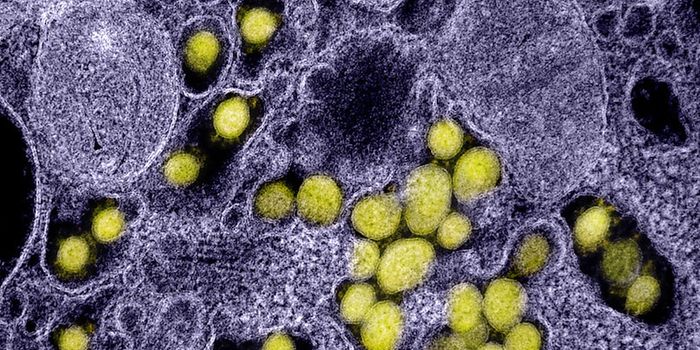

AUG 19, 2020Cell & Molecular BiologyAs the pandemic virus, SARS-CoV-2 continues to cause tens of thousands of new cases of COVID-19 every day in the United ...